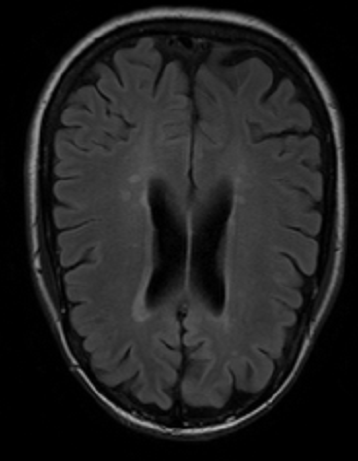

二进制掩码